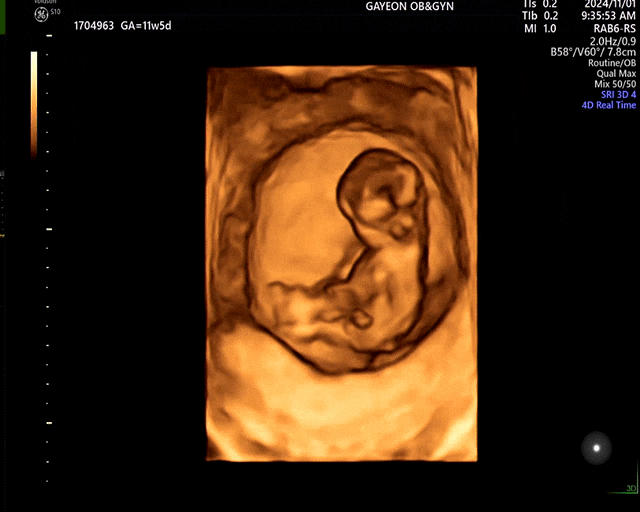

임신 10-11주차 : 태아보험 가입, 첫 정밀초음파와 1차 기형아검사(관악구 보건소)

찐-하! 열허분 우리 조이가 어느덧 3cm가 넘어 머리가 큰 인간이 되었다는 사실,,딱 한 달 전 첫 초음파를 ...